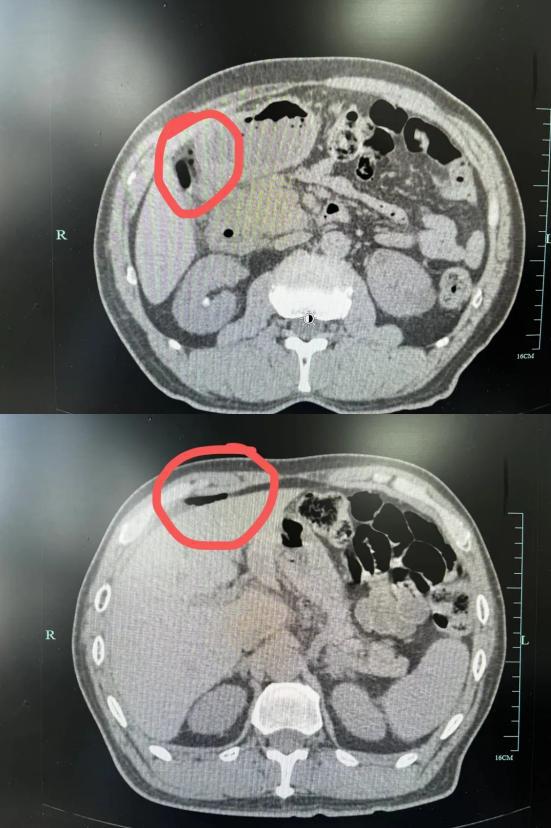

一碗春笋下肚!男子肚子破了个大洞!医生提醒生活

随着天气逐渐回暖,鲜嫩的春菜逐渐成为杭州人餐桌上的主角,但不一定每个人都能享受这份大自然的时令馈赠。...